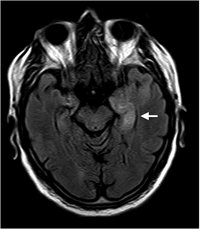

Limbische Enzephalitis

Limbische Enzephalitis - T2

Hyperintensität hippocampal und parahippocampal